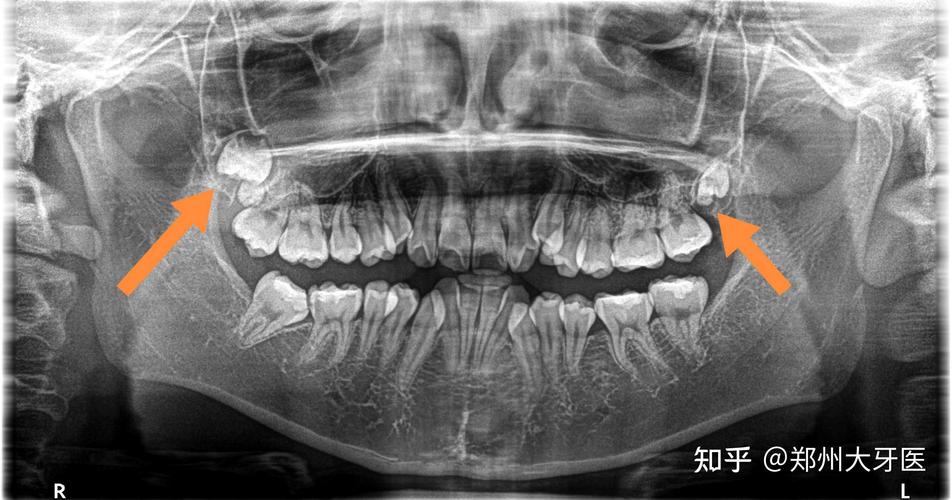

郑州大牙医 的想法: 高位智齿,紧贴上颌窦,风险比较高

上颌高位阻生智齿图片